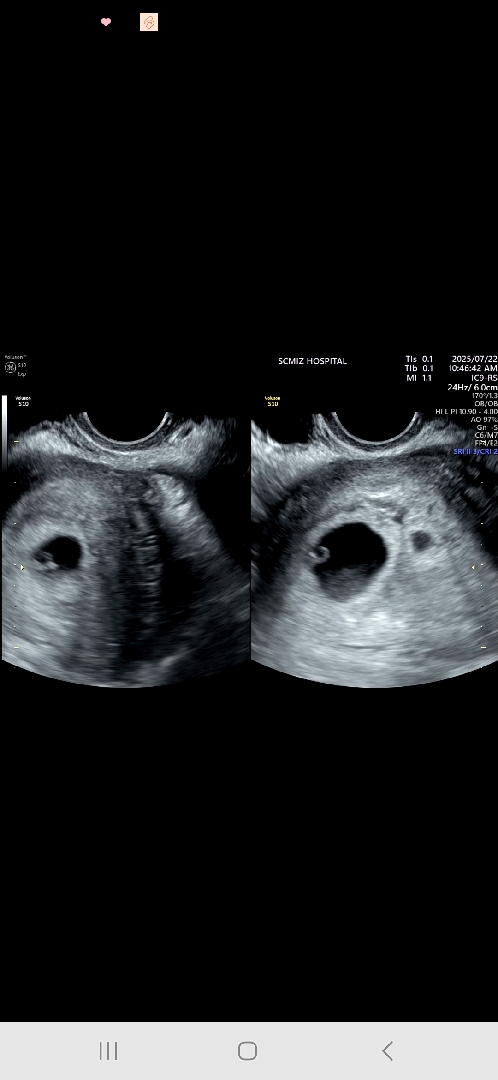

오늘 심장소리듣고 왔어요 열흘전 임신확인하러 갔을때 아기집이 하나라 단태아인줄알았는데 오늘가니 아기집이 하나 더있다네요... 아이가 둘이라니😱 너무 당황스러운데 행복하기도하고 무섭기도하고 어떻게해야하나 싶기도해요 주변에 다태아임산부가 없었어서 완전 무지한데 큰일이에요